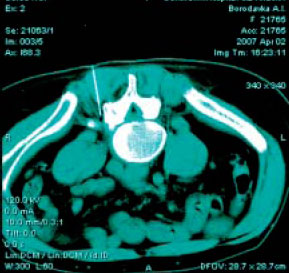

На рис.1 а,б представлены КТ в зоне L4-L5 до и после введения пункционной иглы. На рис.1 а,б представлены КТ в зоне L4-L5 до и после введения пункционной иглы.

С появлением методов визуализации, как, например, рентгеновской компьютерной томографии (КТ) данный вид воздействия принял «конкретные» очертания, давая возможность под визуальным контролем иглу для блокады подводить непосредственно к анатомической структуре, являющейся источником дорсопатии - перифуникулярному пространству в месте компрессии корешка. Этот вид воздействия получил названия малоинвазивной терапии и приносит ощутимый эффект непосредственно после проведения манипуляции, кумулируясь с каждым последующим введением лекарственного препарата и разрывая порочный круг боль – мышечный спазм – боль с выраженным патогенетическим воздействием на болевой синдром. Он широко и успешно применяется во многих странах дальнего и ближнего зарубежья в специально созданных Центрах боли. Методика прицельного введения лекарственных препаратов под контролем визуализации (в нашем случае КТ) врачам нашей клиники была любезно продемонстрирована Mario Wahler, врачом-нейрохирургом из г. Грейфсвальда (Германия), и мы имеем опыт ее положительного использования в нашей практике. На рис.1 а,б представлены КТ в зоне L4-L5 до и после введения пункционной иглы.

На рис.1 а,б представлены КТ в зоне L4-L5 до и после введения пункционной иглы.